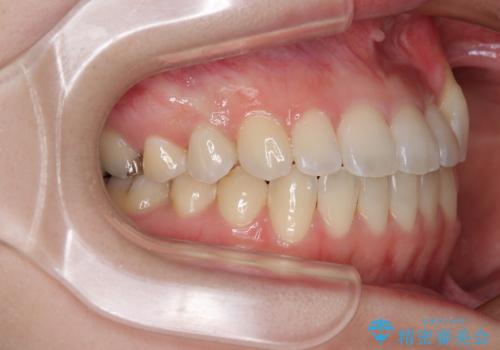

- 上顎の八重歯やデコボコを気にして来院された患者様です。

上顎歯列が狭窄していたため、急速拡大装置により上顎骨を側方に拡大しながら、ワイヤー装置にて矯正治療を行うこととしました。

上顎骨を拡大することで、八重歯やデコボコを歯列に収めることができ、下顎の歯が外に位置していた奥歯の咬み合わせも改善することができました。